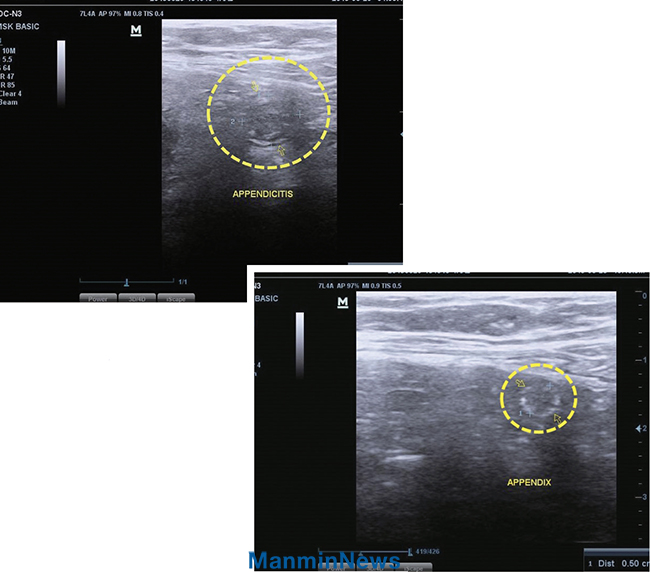

"Ãæ¼öµ¹±â¿°(¸ÍÀå¿°)À» ±ú²ýÀÌ Ä¡·á¹Þ¾Ò¾î¿ä"

Áö³ 3¿ù 22ÀÏ(±Ý), ¿À¸¥ÂÊ ¿·±¸¸®°¡ °á¸®´Â µíÇÑ ÅëÁõÀÌ ´À²¸Áö±â ½ÃÀÛÇß½À´Ï´Ù. °¥¼ö·Ï ÅëÁõÀº ½ÉÇØÁ® ¿À¸¥ÂÊ ¾Æ·§¹è±îÁö »µ±ÙÇÏ°Ô ´À²¸Áú Á¤µµ¿´°í ½Ä¿åµµ º°·Î ¾ø¾úÁö¿ä. µÇµ¹¾Æº¸´Ï ÇÑ ÁÖ°£ ÀüºÎÅÍ ¸öÀÌ ¸÷½Ã ÇǰïÇÑ Áõ»óÀÌ ÀÖ¾ú½À´Ï´Ù.

25ÀÏ(¿ù), ÃÊÀ½ÆÄ °Ë»ç¸¦ ÇØ º¸´Ï Ãæ¼öµ¹±â°¡ ¿°ÁõÀ¸·Î ºÎ¾îÀÖ´Ù´Â Áø´ÜÀ» ¹Þ¾Ò½À´Ï´Ù. Á¤»óÀûÀÎ Ãæ¼öµ¹±âÀÇ Å©±â´Â 0.7cm ÀÌÇÏÀε¥ Àú´Â 1.26cm·Î Ä¿Á® ÀÖ´Ù¸ç ¾ðÁ¦ ÅÍÁúÁö ¸ð¸£´Â »óȲÀ̶ó°í Çß½À´Ï´Ù. ¸ö»ìó·³ ¿ÀÇÑÀÌ µé°í ÁÖº¯¿¡¼ Á¦°Ô Ç÷»öÀÌ ³Ê¹« ¾È ÁÁ´Ù°í ÇßÁö¿ä. Æò¼Ò °®°¡Áö Áúº´À» ¹ÏÀ½À¸·Î Ä¡·á¹Þ¾Æ °£ÁõÇÏ´Â ¼ºµµ´ÔµéÀ» º¸¸ç '³ªµµ Àú·± »óȲÀÌ µÇ¸é Çϳª´Ô²² ¸Ã±æ ¼ö ÀÖÀ»±î?' ÀÚ¹®ÇÒ ¶§°¡ ÀÖ¾ú´Âµ¥, º´¸íÀ» µè°í ³ª´Ï 'ȸ°³ÇÏ°í ±âµµ¹ÞÀ¸¸é µÇÁö' ÇÏ°í ¿ÀÈ÷·Á ¸¶À½ÀÌ Æò¾ÈÇß½À´Ï´Ù.

±×¸®ÇÏ¿© ±×³¯ ¹ã¿¡´Â ÀáÀ» Ç« Àß ¼ö ÀÖ¾ú°í, ´ÙÀ½ ³¯µµ ¾Æ¹«·± ÅëÁõ ¾øÀÌ º¸³¾ ¼ö ÀÖ¾úÁö¿ä. Ä¡·á¹Þ¾Ò´Ù´Â È®½ÅÀÌ µé¾î 28ÀÏ(¸ñ), ÃÊÀ½ÆÄ °Ë»ç¸¦ ´Ù½Ã ÇØ º¸´Ï Ãæ¼öµ¹±âÀÇ Å©±â°¡ 0.5cm·Î ÁÙ¾î Á¤»óÀÌ µÇ¾î ÀÖ¾ú½À´Ï´Ù. ÀÌÈÄ ¸öÀÌ ³Ê¹« °¡º±°í À½½Äµµ Àß ¸ÔÀ» ¼ö ÀÖ°Ô µÇ¾úÀ¸¸ç, Áö±Ý±îÁö ¾ÆÁÖ °Ç°ÇÏ°Ô Áö³»°í ÀÖ½À´Ï´Ù. ÇÒ·¼·ç¾ß!

ÃÊÀ½ÆÄ »çÁø

±âµµ¹Þ±â Àü_ Ãæ¼öµ¹±â°¡ ¿°ÁõÀ¸·Î ÀÎÇØ 1.26cm·Î ºÎ¾îÀÖÀ½(Á¤»ó 0.7cmÀÌÇÏ)

±âµµ¹ÞÀº ÈÄ_ ºÎ¾îÀÖ´ø Ãæ¼öµ¹±â°¡ 0.5cm Å©±â·Î °¨¼ÒÇÔ